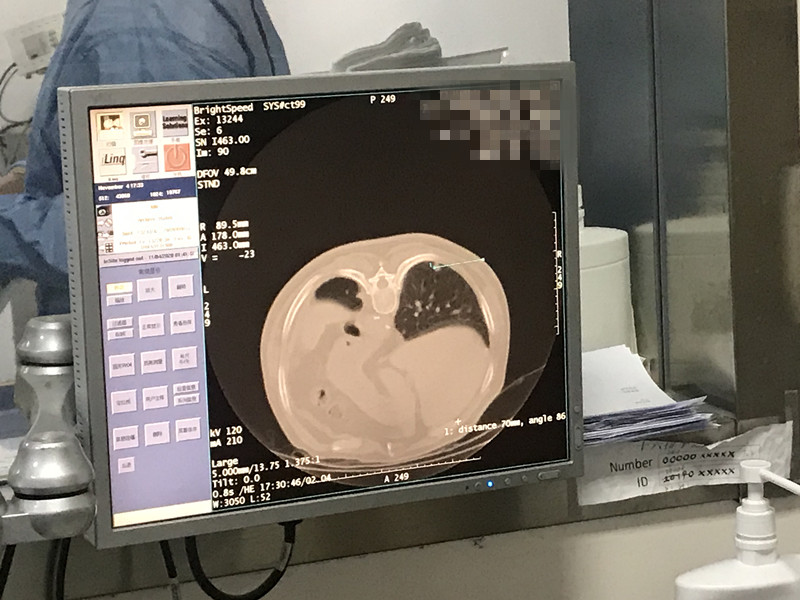

79岁患者肺部氩氦刀冷冻消融

发布人:美国氩氦刀技术官方网站    发布时间:2020/11/16 15:15:03